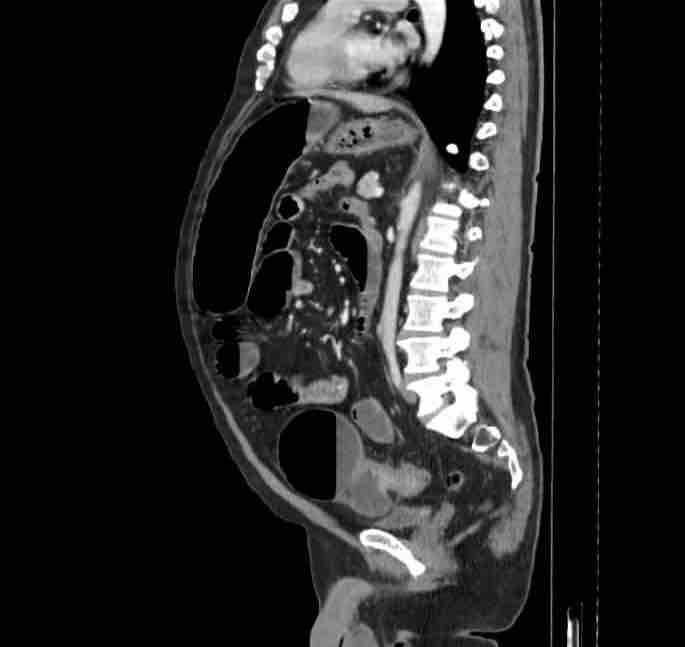

Hello, once again I’m making another Gofundme for my dad. As some of you may know he was deported back in December, he has been extremely ill before and even worse after the lack of treatment and medical necessities, he has recently gotten a CT scan that shows an obstruction in a segment of the colon called the sigmoid colon and needs a sigmoidectomy. He was advised by the providers in Mexico to have an emergency surgery done this is life or death. We are sadden by the news we were not hoping for this, they are asking for 15,000 in order to get the surgery done. We are completely helpless due to the fact of distance and we are unable to help my dad. Anything helps, please share

Hola, una vez más estoy creando otra campaña de Gofundme para mi papá. Como algunos saben, fue deportado en diciembre. Ha estado muy enfermo antes y aún peor después de la falta de tratamiento y atención médica. Recientemente le realizaron una tomografía computarizada que muestra una obstrucción en un segmento del colon llamado colon sigmoide. Los médicos en México le recomendaron una cirugía de emergencia; es cuestión de vida o muerte. Nos entristece la noticia; no esperábamos esto; piden 15,000 para la cirugía. Estamos completamente indefensos debido a la distancia y no podemos ayudar a mi papá. Cualquier ayuda nos ayuda, por favor, compártala.